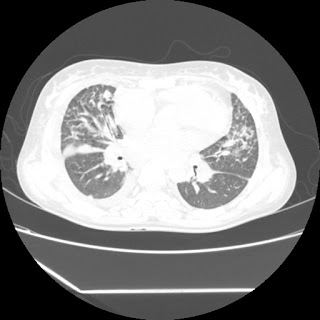

(HRCT)CT-Scan investigation done on 19Aug15 :

Series3